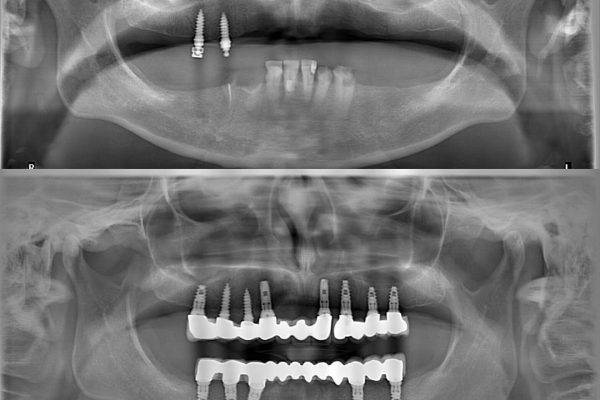

All on 4 und All on 6

Zahnimplantate

In unserer Partner Klinik werden

bereits

über 10.000

Implantate

eingesetzt.